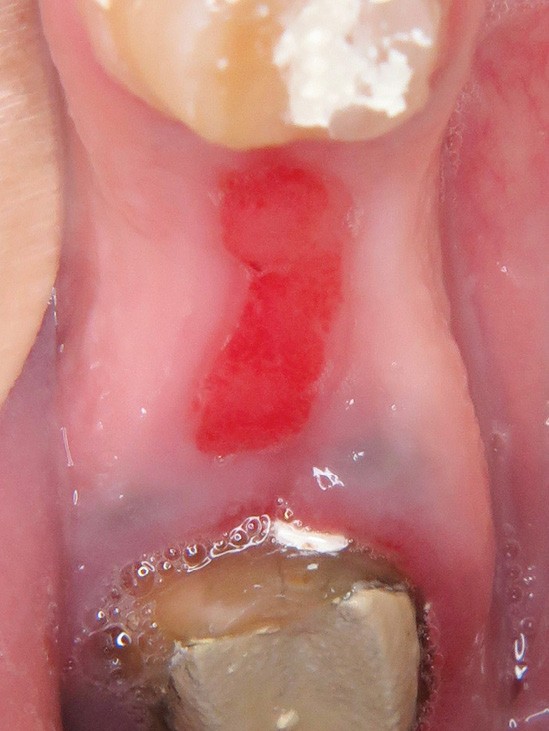

1. Épulis inflammatoire (plasmocytaire)

- Nodule indolore, pédiculé, érythémateux, parfois ulcéré (fig. 1a).

4. Épulis postextractionnel

- Granulome intra-alvéolaire à la suite d’une avulsion dentaire (fig. 4a et b).

- Absence de cicatrisation spontanée.